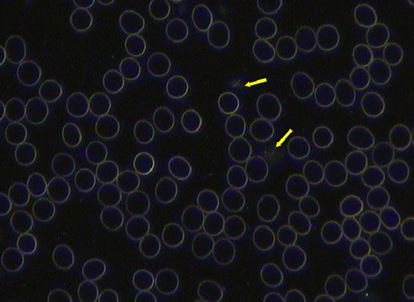

Before

Live blood analysis taken during January 2013 shows he was inflamed and lacked nutrition. Red blood cells which appear to have glowing half circles in their centre are called annulocytes. When they appear in this way it indicates dehydration and/or a lack of iron. The clumping of the red blood cells indicate inflammation and is called erythrocyte aggregation.

After

Live blood analysis taken during February 2014 shows a dramatic change in the blood. Cells are hydrated and floating independently of each other. A much more healthy reading.